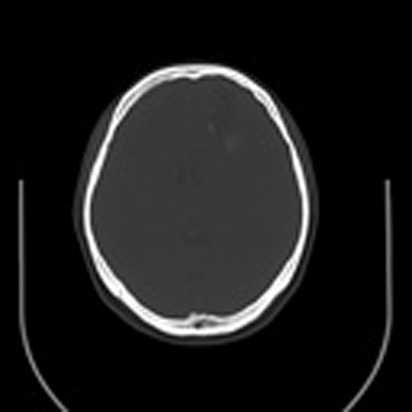

标题: CT16829:女,36,近20天偶有口眼歪斜短暂发作史,近日头痛。 [打印本页]

标题: CT16829:女,36,近20天偶有口眼歪斜短暂发作史,近日头痛。

近20天偶有口眼歪斜短暂发作史,近日头痛。患者先做ct发现病变后又做了mri检查,前日上传2次ct图像均未成功,今日补上。

大脑中线部位肿瘤向两侧生长,可见明显钙化影,考虑少枝胶质瘤,建议增强除外脑膜瘤

左额混杂密度肿块,经胼胝体跨越中线向右额叶生长,多考虑少支胶质细胞瘤,建议mr增强扫描,待排除血管畸形。